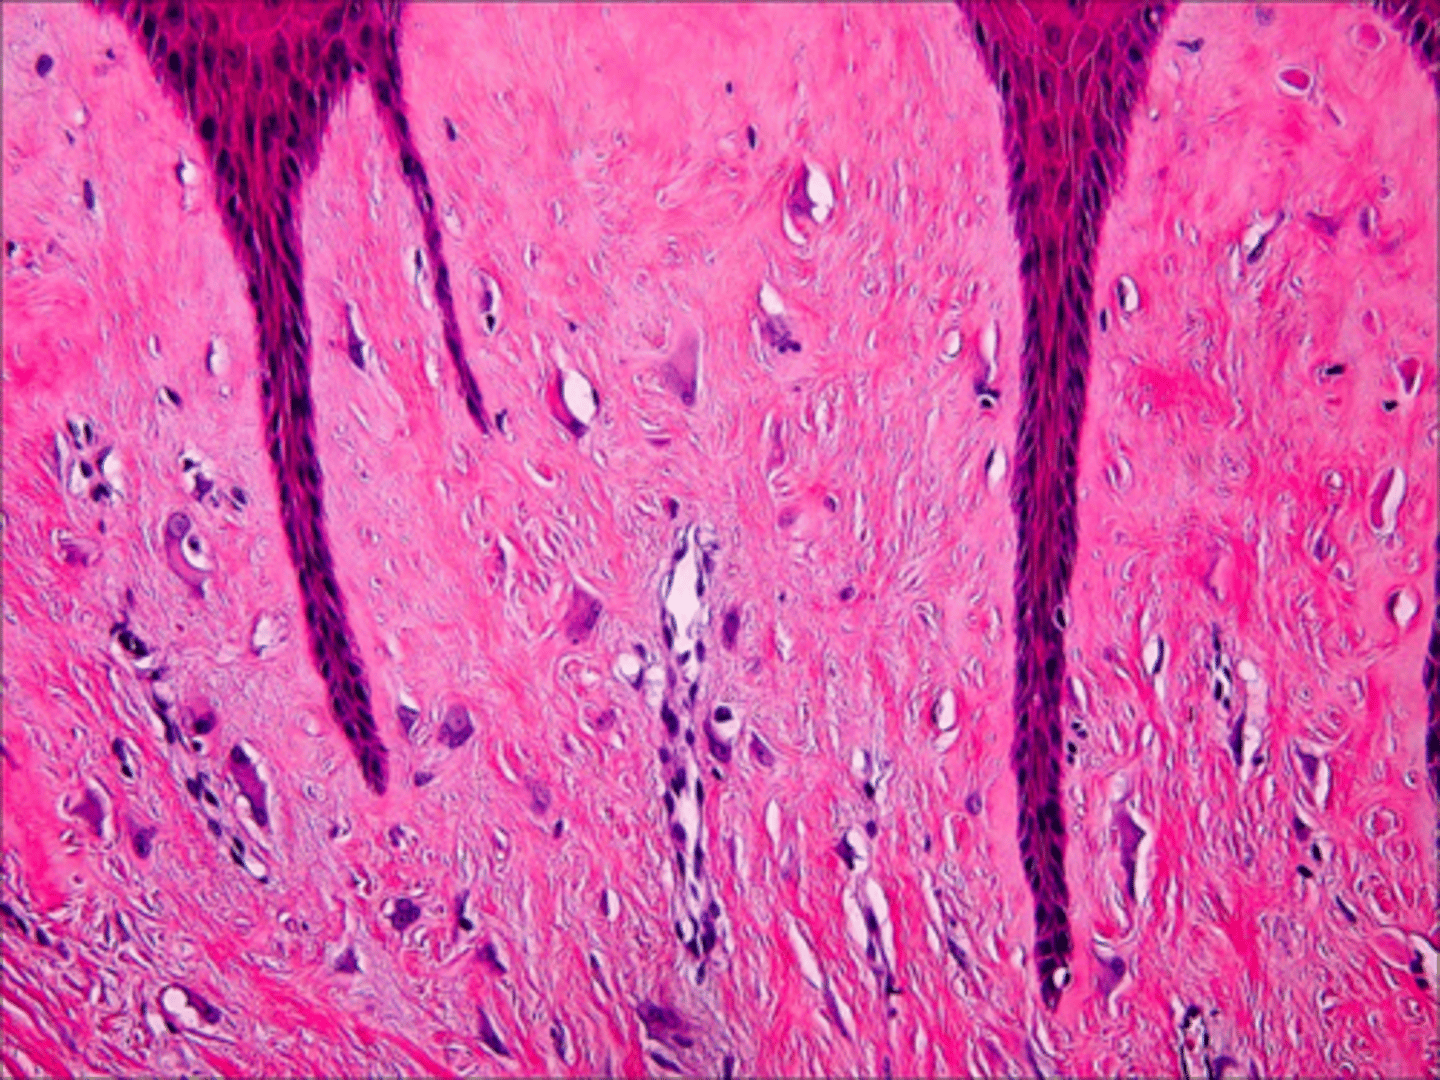

Granular Cell Tumor

Patient presents with a yellowish growth on the dorsolateral tongue surface. Histopathology showed Abundant pale, eosinophilic granular cytoplasm and pseudoepitheliomatous hyperplasia. What do you suspect?

Granular Cell Tumor

Abundant pale, eosinophilic granular cytoplasm and pseudoepitheliomatous hyperplasia is associated with what pathology?

Giant Cell Fibroma

which of the following is NOT associated with presenting yellow?